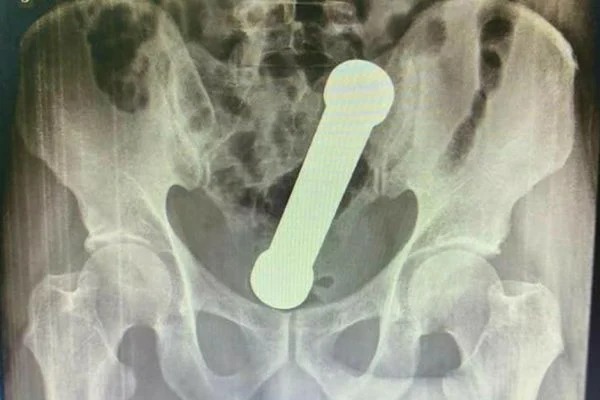

Médicos encontram peso de academia dentro de paciente em Manaus (Foto: International Journal of Surgery Case Reports/ Reprodução)

Médicos encontraram um peso de dois quilos, e cerca de 20 centímetros de comprimento dentro de um homem de 54 anos, em Manaus. O peso é dos mesmos usados em academias de ginástica para exercícios de braço. O fato inusitado rendeu um relato de caso publicado na plataforma científica International Journal of Surgery Case Reports na última quarta-feira (6).

Raio-X detectou o peso dentro do homem

Ao realizarem um exame de raio-X, os médicos encontraram um peso, dentro do homem. Segundo as imagens, o haltere estava entre o reto e o intestino grosso do paciente, que, depois do exame, admitiu ter introduzido o peso de academia no corpo para obter satisfação sexual.